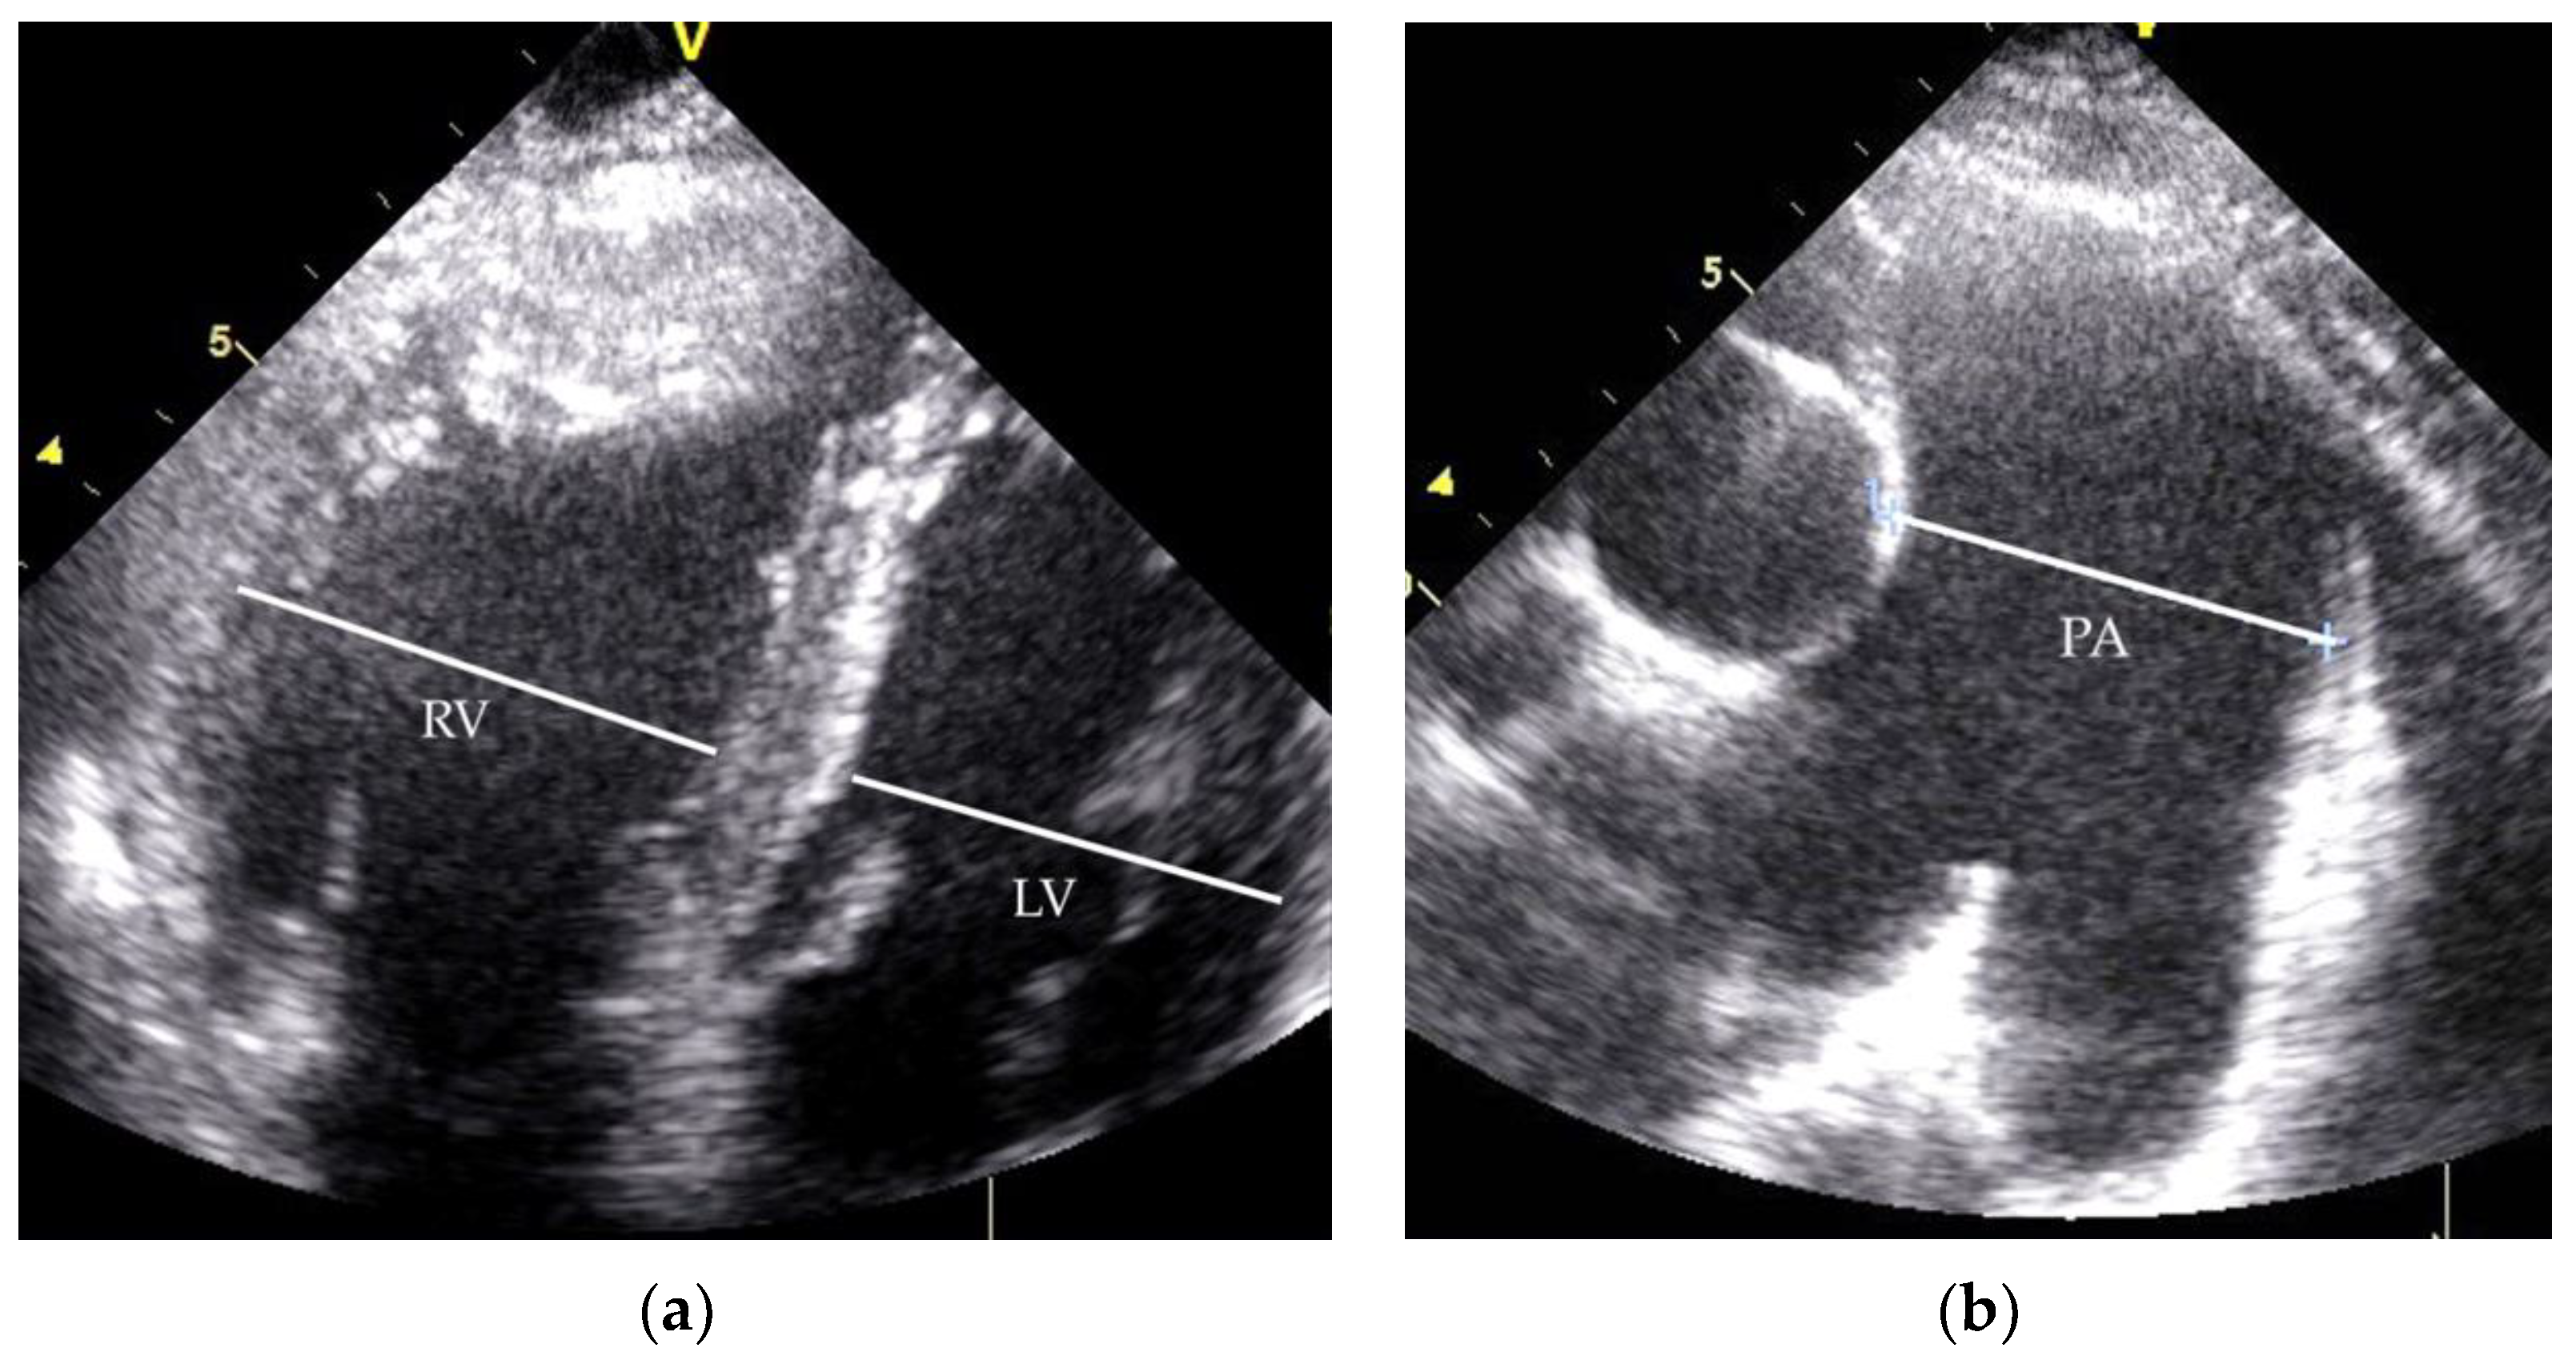

| RHC Parameters | Time of Diagnosis | Before Initiation of the Specific Therapy |

|---|---|---|

| mPAP (mmHg) | 58 | 65 |

| PVR (WU) | 8.5 | 7.2 |

| PCWP (mmHg) | 9 | 2 |

| CO (L/min) | 5.8 | 8.7 |

| Before ST | 1 Year of ST | 5 Years of ST | 10 Years of ST | |

|---|---|---|---|---|

| 6MWT (m) | 560 | 710 | 708 | 640 |

| NYHA class | II-III | I | I | II |

| TR grad. (mmHg) | 65 | 55 | 50 | 67 |

| TAPSE (mm) | 27 | 29 | 25 | 28 |

| PA diameter (mm) | 42 | 45 | 52 | 53 |